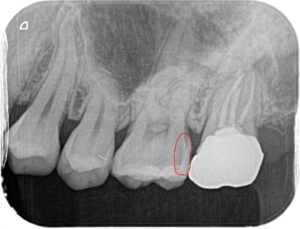

写真の赤丸が虫歯の部分です。